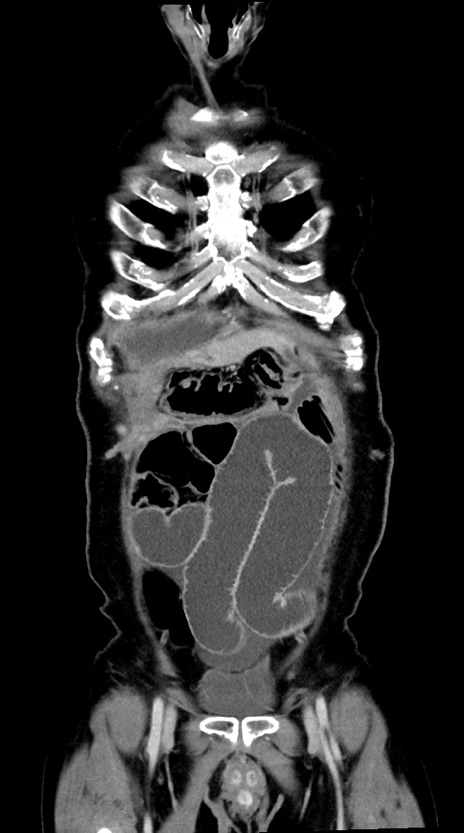

症例28(冠状断像)

【症例】60歳代男性

【主訴】嘔吐

【現病歴】胃癌にて胃全摘後。食思不振が悪化し、夜中に嘔吐することがある。

【既往歴】胃癌、胃全摘、脾摘、胆摘後

【データ】WBC 5900、CRP 10.56